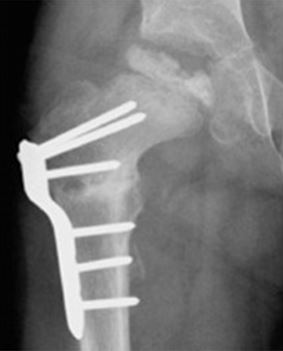

The most common surgical procedure for treating Perthes disease is an osteotomy. In this type of procedure, the bone is cut and repositioned to keep the femoral head snug within the acetabulum. This alignment is kept in place with screws and plates, which will be removed after the healed stage of the disease.

In many cases, the femur bone is cut to realign the joint. Sometimes, the socket must also be made deeper because the head of the femur has actually enlarged during the healing process and no longer fits snugly within it.